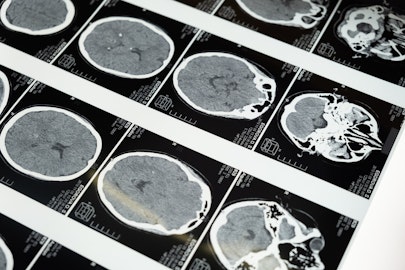

中枢神経系(脳や脊髄)の異常や、各種中毒物質の摂取によって見られることがあります。また高齢犬が立ち上がろうとする時に後肢に震えが見られるのも、このミオクローヌスです。